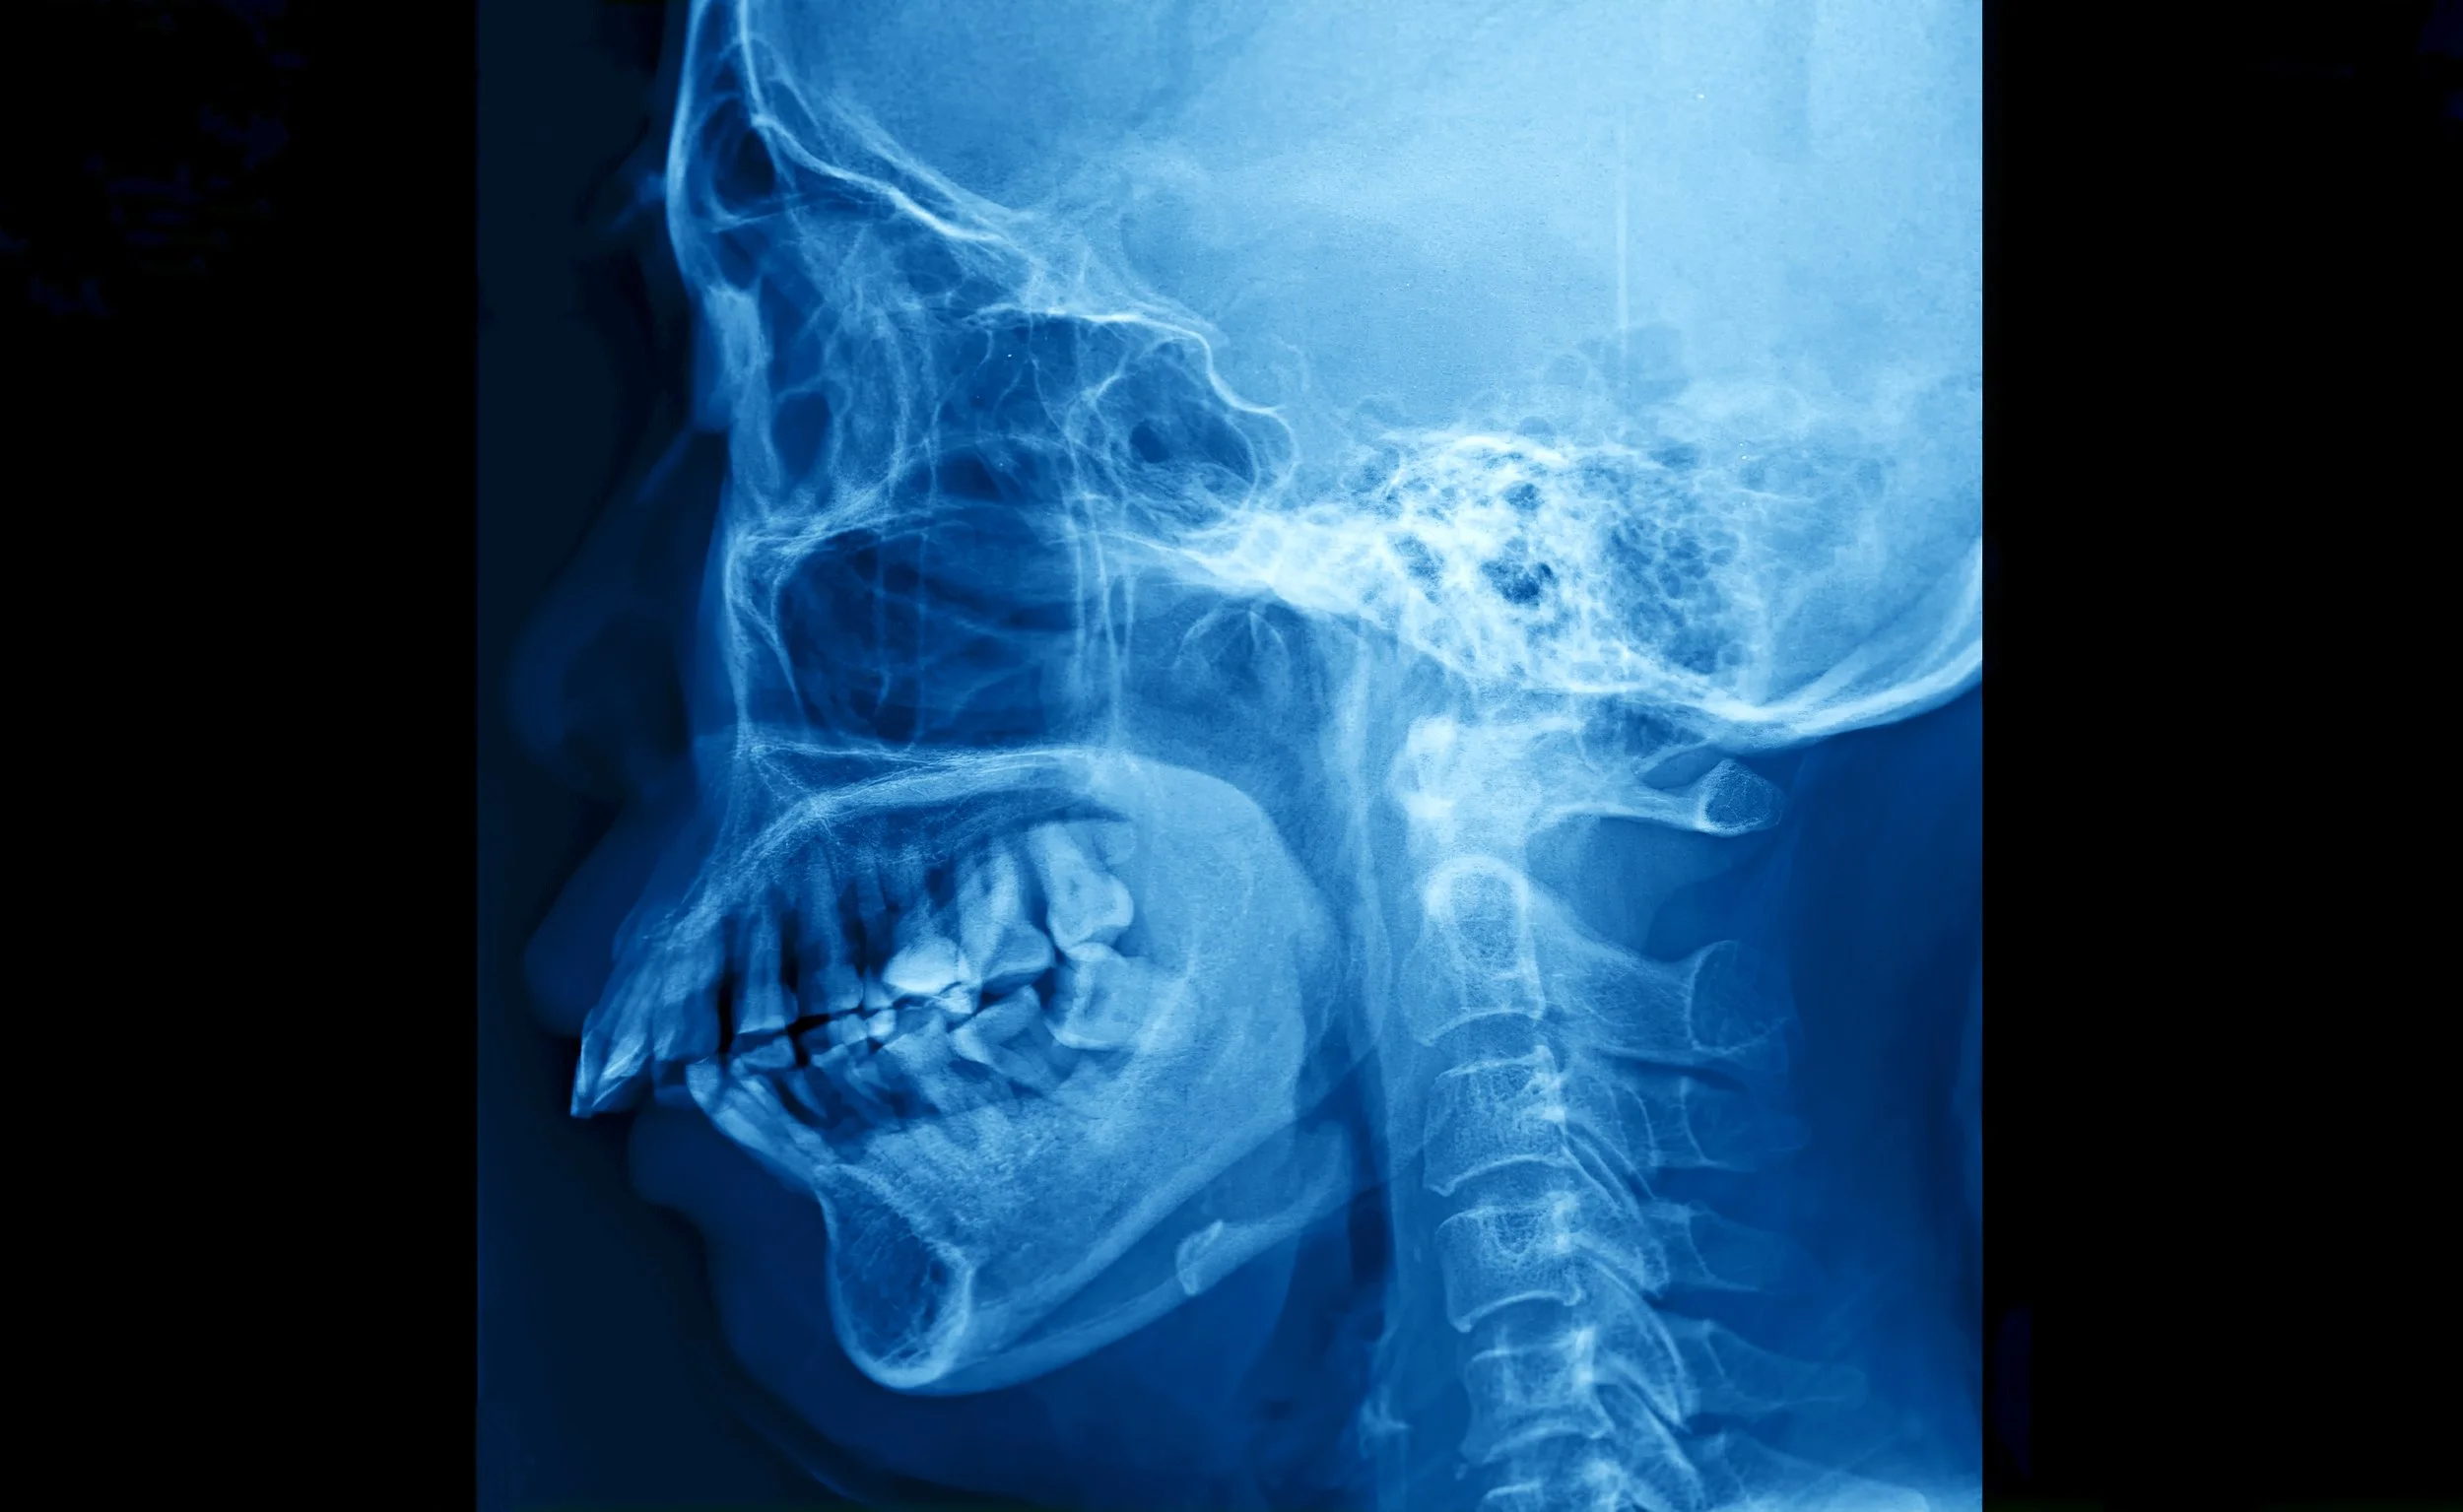

What Is The TMJ?

The temporomandibular joint, or TMJ, connects your jawbone to your skull and controls the movements of your mouth. This joint allows you to open and close your mouth smoothly and is essential for chewing, speaking, and yawning. You have one TMJ on each side of your face.